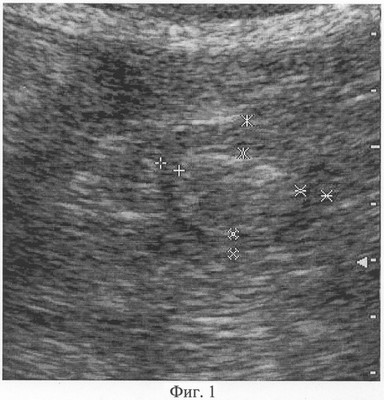

При фиксации изображения в момент полного раскрытия просвета гастродуоденального перехода осуществляют измерение толщины его мышечного слоя, который визуализируется как широкая гипоэхогенная полоска с четкими контурами, расположенная по периферии ультразвукового поперечного среза. Причем измерение толщины производят по передней, верхней, задней и нижней стенкам гастродуоденального перехода, как показано на Фиг.1. Аналогичным образом проводят измерение толщины мышечного слоя гастродуоденального перехода в фазу максимального его смыкания, как показано на Фиг.2.

Фиг.1. Сканограмма (режим серой шкалы, поперечная проекция) гастродуоленального перехода: фаза полного раскрытия просвета, толщина мышечного слоя R1=4,8 мм, R2=5,9 мм, R3=3,4 мм, R4=3,6 мм.